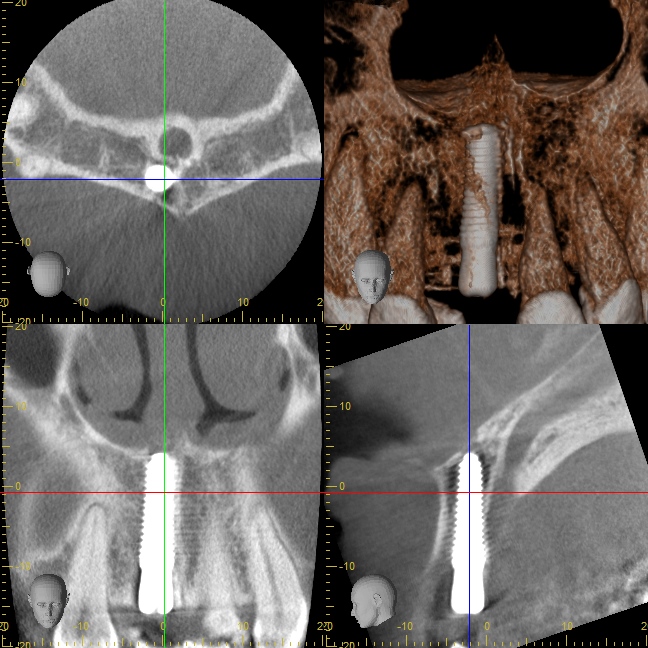

オペ中の口腔内写真とCT写真